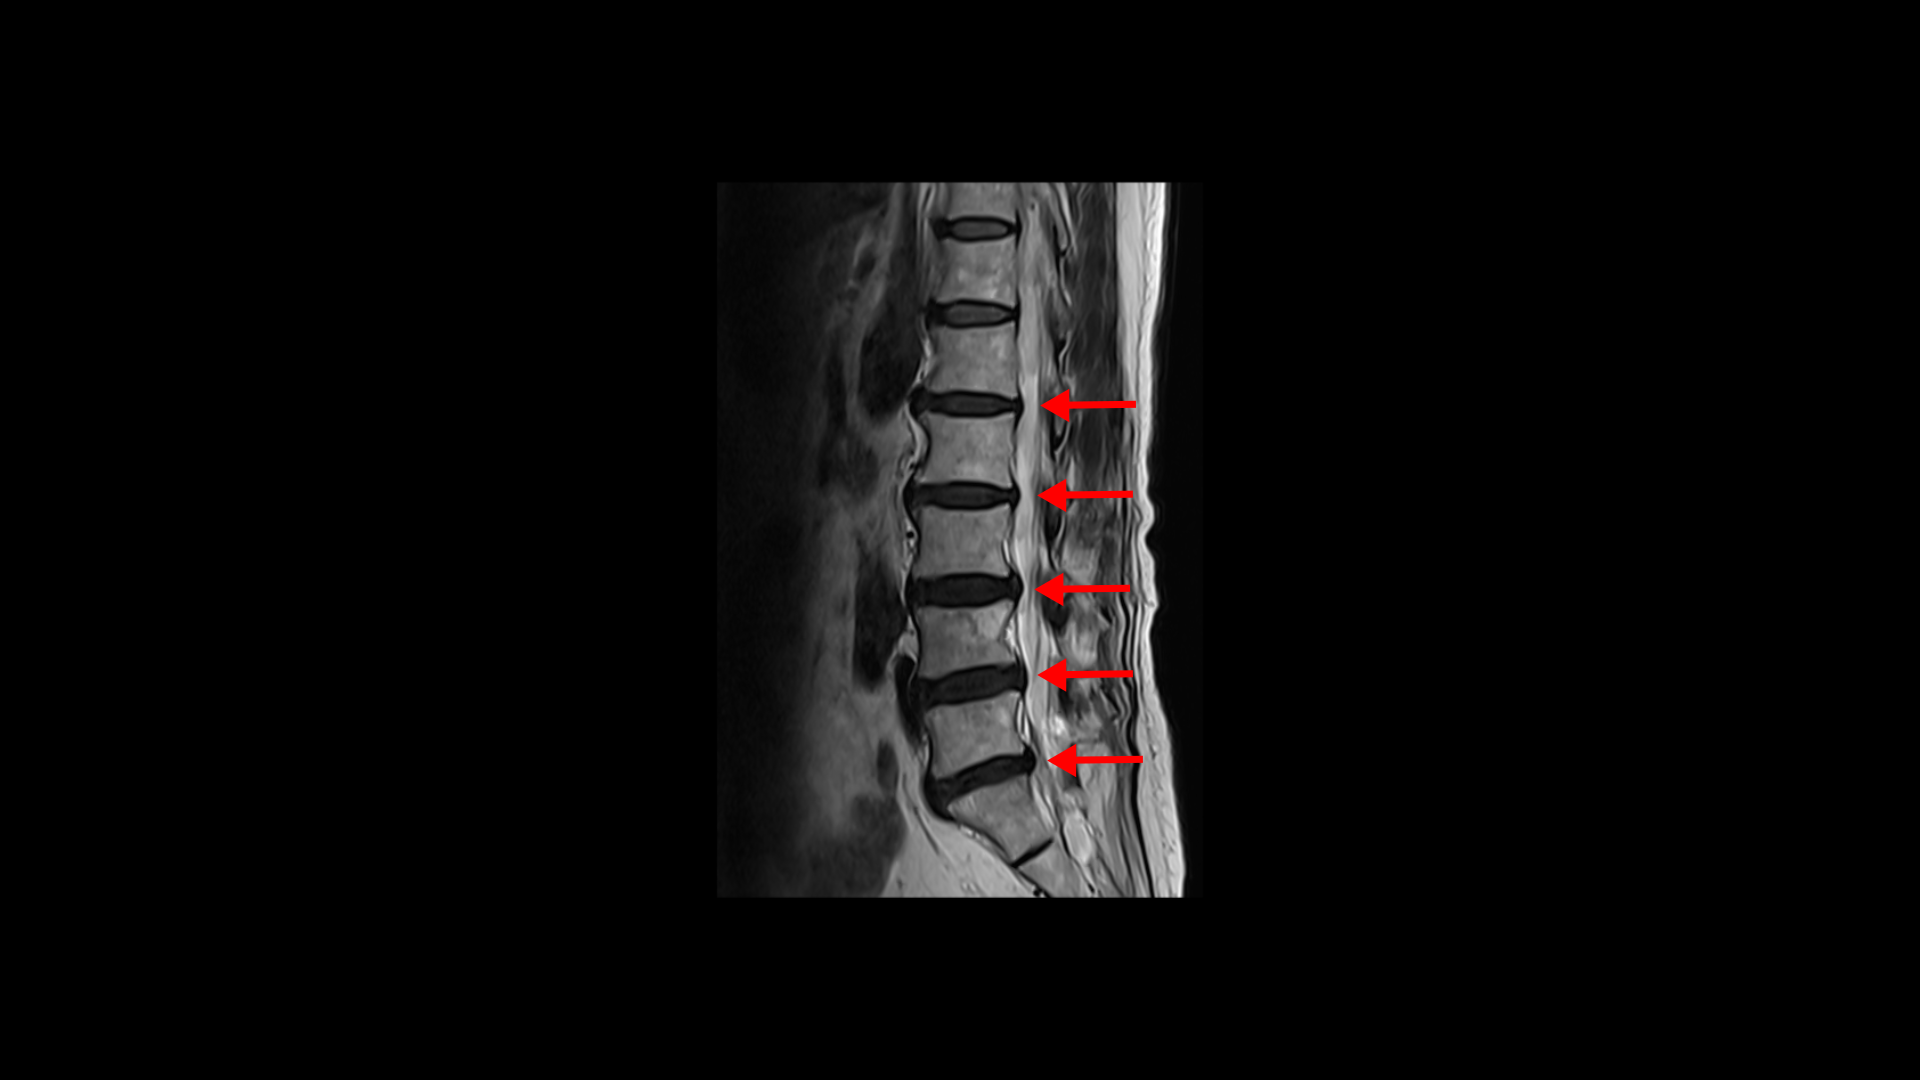

이분 MRI를 보면 74세의 연세답게 여러 마디의 퇴행성 디스크가 있습니다. 하지만 심하지 않습니다.

3번 4번에 황색 인대가 조금 두꺼워진 중심성 협착이 보이지만 역시 심하지는 않습니다.

좌우의 신경구멍도 막힌 곳이 없습니다.

그런데 이런 환자분들 중 협착이 조금이라도 보이니까 협착증 환자로 오진되어 협착증 치료만 받고 계신 분들도 많습니다.